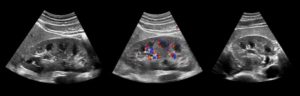

Образования, вызывающие сверхсильное отражение, чаще возникают в паренхиме и почечных пирамидах и могут проявляться на экране белыми точками и пятнами различных размеров (см. фото).

На мониторе при ультразвуковом обследовании высвечивается белое пятно, которое является лишним элементом структуры, и врач сразу определяет наличие или отсутствие акустической тени. Это является определяющим моментом для установления плотности гиперэхогенного включения.

Метод УЗ-исследования основан на степени отражения ультразвука от тканей различной плотности. Гиперэхогенность – это усиление акустической тени, то есть на практике это значит, что структура органа имеет высокую плотность и хорошо отражает ультразвук. На мониторе это выглядит как более светлая, почти белая область.

У почечных пирамид параметр эхогенности ниже и на дисплее визуально они выглядят в виде отдельно располагающихся треугольных структур. Если звуковая волна упирается в преграду, состоящую из плотного новообразования, то она сквозь него не проникает, а отражается, образуя акустическую тень. Такие патологические образования или включения на мониторе прибора смотрятся в виде белого пятна.